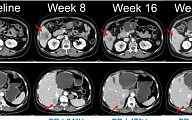

한미약품, 흑색종 항암신약 ‘벨바라페닙’ 임상 2상 첫 환자 투약

[BioS]한미약품, 'pan-RAF' NRAS 흑색종 국내 2상 "첫 투약"